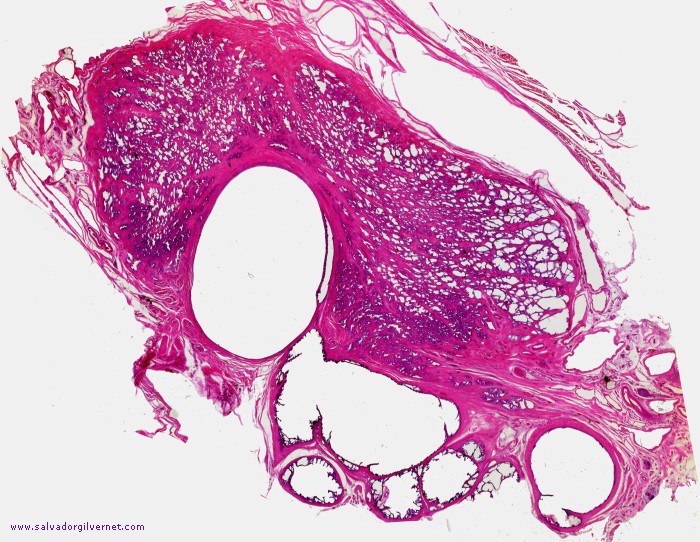

Quiste utricular

• Serie R-1

• Pieza de necropsia

• Sección frontal oblicua que interesa la porción proximal del conducto eyaculador derecho, ampolla deferencial y vesícula seminal derecha. Quiste de utrículo y porción proximal del conducto eyaculador, ampolla deferencial y vesícula seminal muy dilatados (Detalle 1)

Tinción HE

• ca. 1945